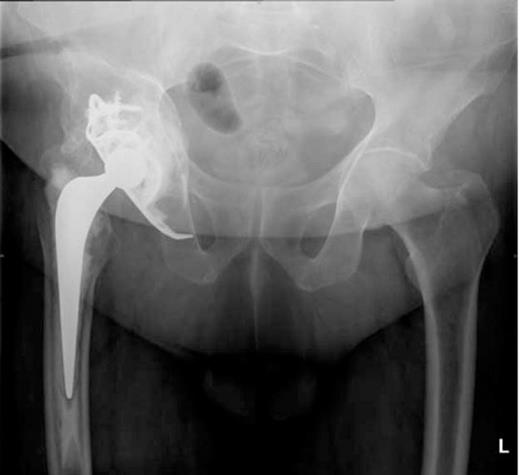

To avoid thrombus escaping from the iliac vein at the time of revision, a vena cava filter was inserted from the contralateral femoral vein (Figure 3).

Inferior vena cava (IVC) filter inserted prior to revision surgery